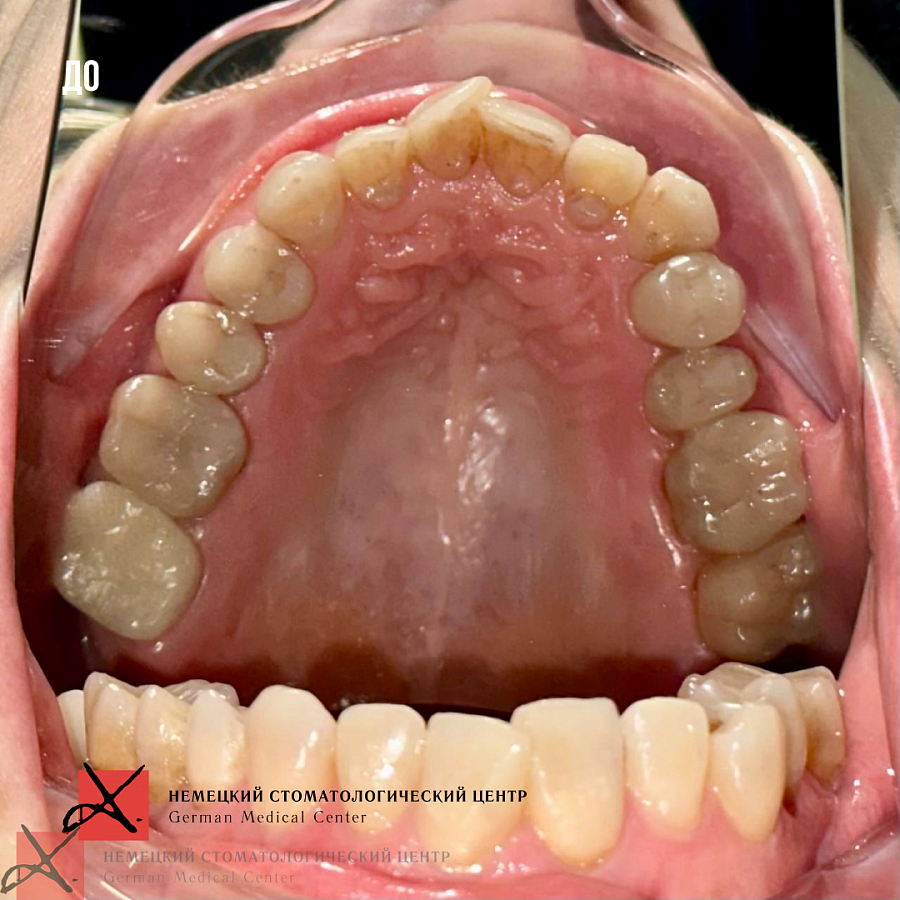

Пациентка 57 лет обратилась с жалобами на сильную боль ощущения в левом височно-челюстном суставе. Также пациентку беспокоил эстетический дефект в виде скученности зубов.

На данный момент пациентка в процессе ортодонтического лечения брекетами. Боли в ВНЧС ушли. Промежуточный результат по эстетической части уже впечатляет (и нас, и пациентку).